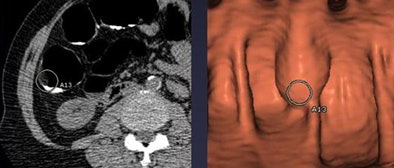

![]() |

| Above, a false-positive CAD mark highlights a submucosal lipoma. All images courtesy of Dr. Perry Pickhardt. |